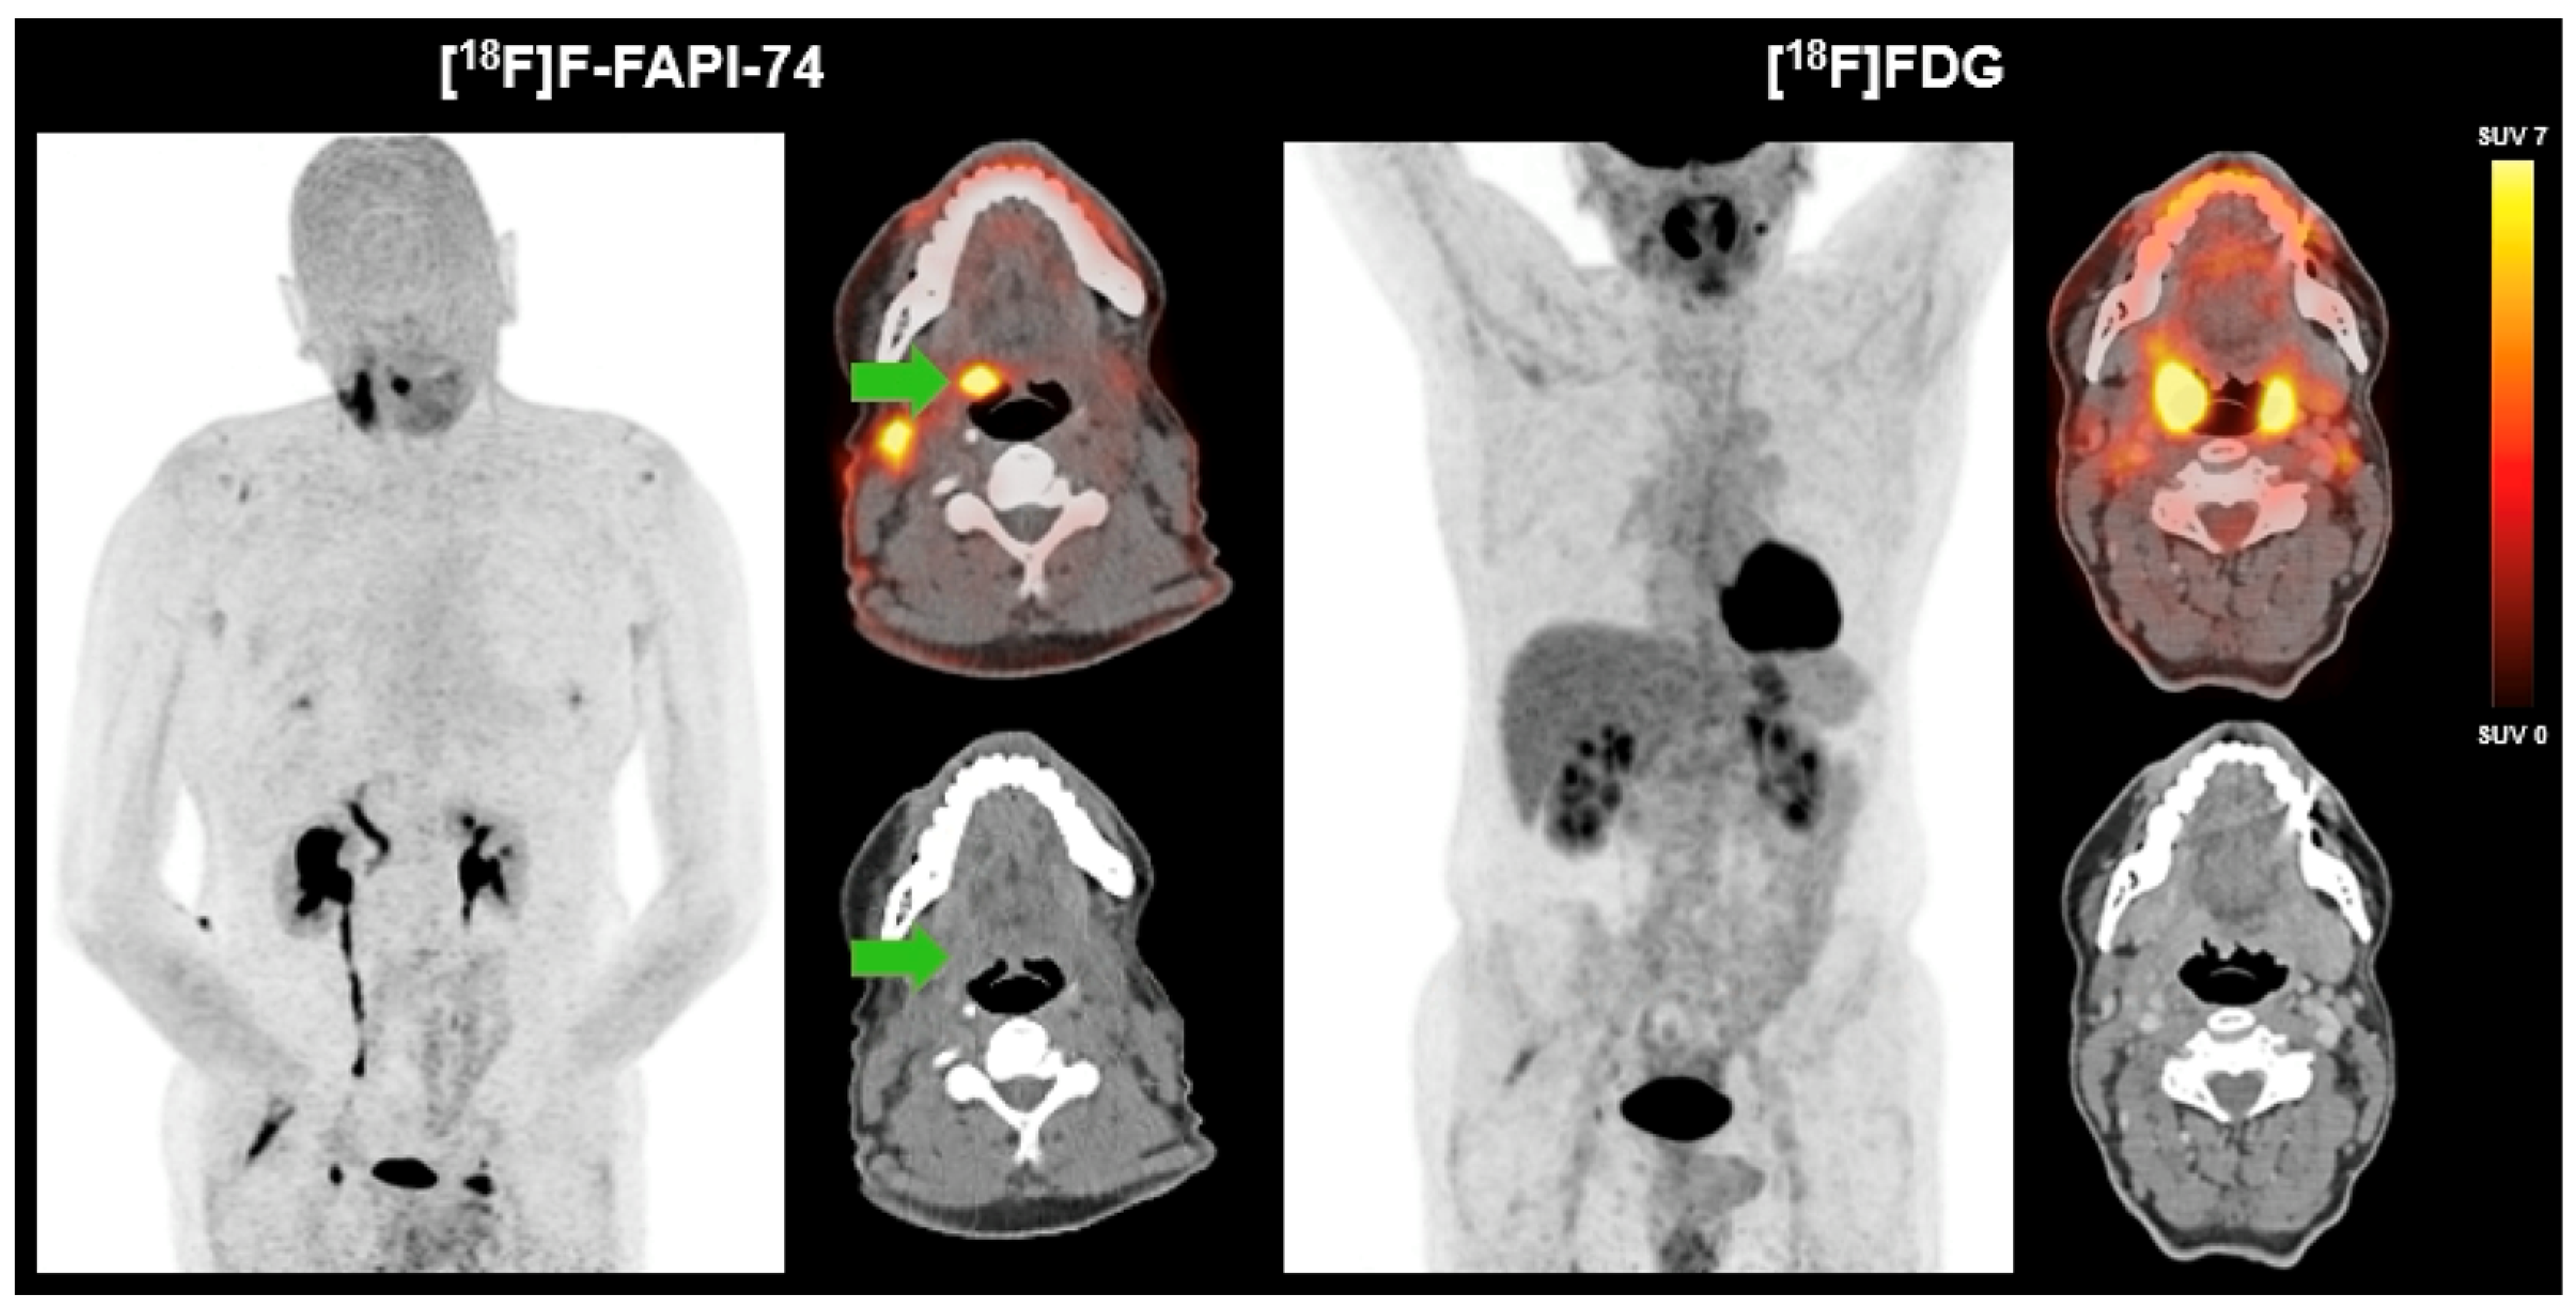

We present a 60-year-old male patient who presented with a two-year history of right-sided cervical soft tissue swelling. MRI revealed a well-circumscribed, spherical lesion in the right mandibular angle with cystic-regressive components and strong contrast enhancement. Furthermore, multiple enlarged lymph nodes were observed bilaterally in the mandibular angle and along the vascular nerve sheath. The enhancement of contrast in the right lingual tonsil was deemed to be reactive. The preliminary differential diagnosis included lymphoma. Surgical excision of the lesion revealed a partially cystic-necrotic lymph node metastasis (maximum diameter 4.7 cm) of a moderately differentiated, keratinizing SCC without extracapsular spread. The presence of strong p16 expression was indicative of a probable association with human papilloma virus, with the oropharynx being identified as the presumed primary site. As no definitive primary tumor could be identified on initial imaging or clinical examination, the case was classified as HNCUP. FDG-PET/CT revealed symmetrical metabolic activity in the Waldeyer’s ring and a suspicious FDG-avid lymph node in the left upper vascular nerve sheath, but no distinct FDG-avid primary lesion. Subsequent [18F]F-FAPI-74-PET/CT demonstrated focal FAP expression in the right palatine tonsil, raising suspicion of a tonsillar carcinoma, as well as increased FAPI uptake in correlation with postoperative changes following lymph node dissection. In contrast to FAPI-PET/CT, no morphologically distinct lesion could be delineated in the region of the right palatine tonsil on CT. No further evidence of a FAP-expressing malignancy was detected (Figure 1). Definitive histopathology of the excised right tonsil and right tongue base confirmed infiltrates of a non-keratinizing, p16-positive SCC (pT2, pN2a [1/18, 4.7 cm], L0, V0, Pn0), with all surgical margins being negative (R0).

Figure 1.

FAPI-PET/CT versus FDG-PET/CT in HNCUP.

In a 60-year-old male patient with HNCUP following lymph node excision of a partially cystic-necrotic lymph node metastasis of a moderately differentiated, keratinizing SCC without extracapsular spread, FDG-PET/CT showed no definitive evidence of a metabolically active primary tumor. There was diffusely increased but largely symmetrical FDG uptake in the Waldeyer’s ring and a single suspicious FDG-avid lymph node in the left upper cervical level along the vascular nerve sheath. In contrast, [18F]F-FAPI-74-PET/CT demonstrated focal, intense FAP expression in the right palatine tonsil (green arrow), suggestive of a primary tonsillar carcinoma. On CT, no morphologically distinct lesion could be delineated in the region of the right palatine tonsil, underlining the added diagnostic value of FAPI-PET in identifying the primary tumor site. Additionally, a diffuse FAPI uptake in the surgical bed following lymph node excision consistent with postoperative changes was detected. Definitive histopathology confirmed infiltrates of a non-keratinizing, p16-positive SCC.